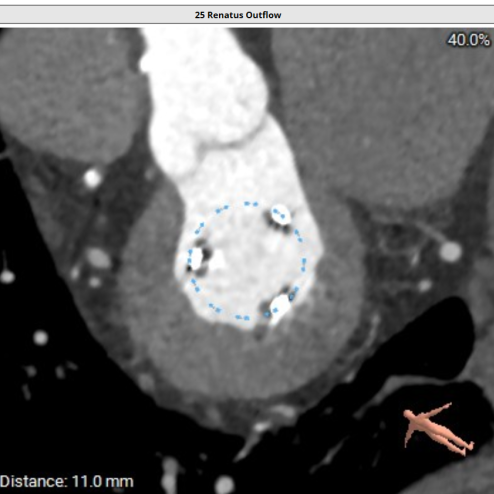

二尖瓣生物瓣架内径23mm,外径25mm,根据瓣架形态,符合25#Mosaic瓣膜

模拟23#Renatus植入

模拟25#Renatus植入